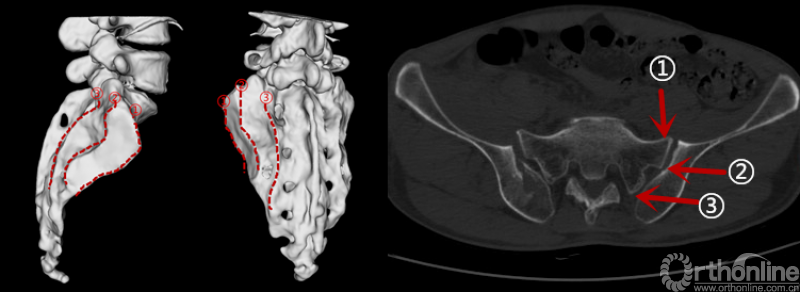

新月形骨折Day分型的缺陷给临床应用带来困扰[4、5],本研究中的65例新月形骨折患者按照Day分型无法分入任何一型或分型在CT横断面不同层面存在变化的有27例,占比41%(27/65)(图6)。因此,迫切需要建立一个更加有效、实用的新月形骨折分型。

骶髂关节的解剖结构

骶骨和髂骨对应的凹陷的沟槽和隆起的骨嵴犬牙交错[8],生理状态下增加了关节间的摩擦系数,增加关节的稳定性[6-8]。骶髂关节复杂的解剖结构决定了不能将其均一化看待。而Day[9]等将复杂的骶髂关节三等分,并据此分型显然是有很大的问题的。

骶骨在骶髂关节水平主要有3道明显隆起的骨嵴,即骶骨耳状面前缘(骶骨翼),骶骨耳状关节面后缘(骶骨侧嵴),还有后方的骶骨外侧嵴。这些骨嵴与骶髂间的韧带如骶髂前韧带、骶髂骨间韧带、骶髂后韧带和髂腰韧带等相互作用,产生“核桃钳子”(Nutcracker)效应[7、8],即在侧方挤压暴力下,在骶髂偏前方产生压应力,而骶髂后方的韧带复合体产生张力。在侧方挤压暴力导致的骶髂偏前方的压应力作用下,偏前方的突出的骨嵴(骶骨翼、骶骨侧嵴)可能成为顶破相应髂骨处的支点。

另外,与骶骨突出的骨嵴相对应的是髂骨上的凹陷部分,则成为髂骨的相对薄弱点,从而更容易在此处产生髂骨的骨折,即新月形骨折解剖分型的Ⅰ、Ⅱ型。后方的骶骨外侧嵴则是通过强大的韧带结构和髂骨相连,在侧方挤压导致的骶髂后方张力作用下[8],更容易产生髂骨的撕脱骨折,即新月形骨折解剖分型的Ⅲ型。

通过CT轴位和冠状位多层面的观察,发现新月形骨折线通常出现在骶髂关节处,跟骶骨在骶髂相接部分突出的骨嵴和髂骨上的凹陷密切相关。骶骨在骶髂关节的骨嵴主要有三道,骶骨翼,骶骨侧嵴和后方的骶骨外侧嵴。其中骶髂关节中骶、髂骨质能紧密接触的主要是骶骨翼和骶骨侧嵴。这两处骨嵴在其对应的髂骨处均有相应的凹陷。

在骶骨翼水平,骶髂关节经前方的骶髂前韧带联合为一体,一体化的骶髂显然强于单纯的髂骨,所以侧方挤压暴力下,髂骨翼的骨折线起自骶髂关节(新月形骨折I型)或者骶髂关节略前方[3],即为病理解剖学分型Ⅰ型。

侧方挤压作用力下,产生的作用力对骶髂关节前半是挤压力,后部是牵张力[10]。在骶骨侧嵴水平,突出的骶骨侧嵴对髂骨内板相当于支点,侧方挤压暴力作用下,在局部产生骨折。即为病理解剖学分型Ⅱ型。

骶骨后方外侧嵴距离髂骨后缘有一定距离,主要为韧带附着点,在侧方挤压暴力作用下,骶髂后方产生张力,所以其骨折主要表现为髂骨的撕脱骨折,即为病理解剖学分型Ⅲ型。